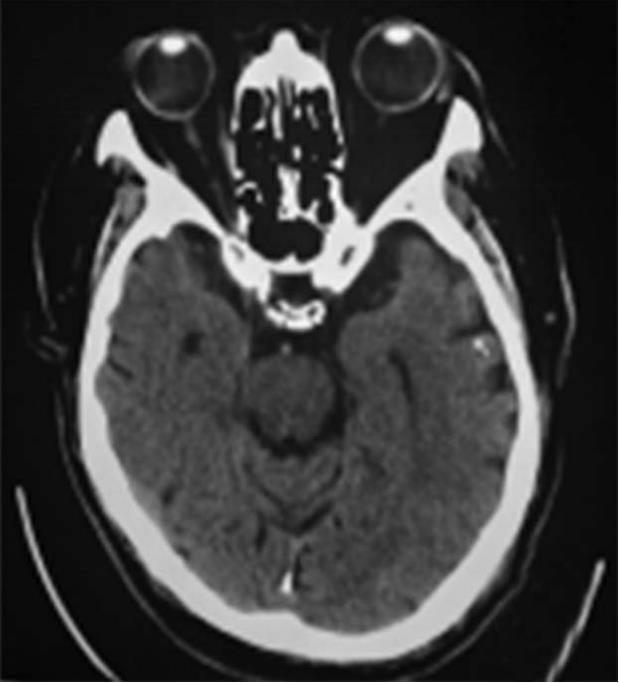

3.治疗概要 入院后完善相关检查,考虑超早期缺血性脑卒中。给予rt-PA替普酶静脉溶栓,24h后予抗血小板聚集等治疗,但效果欠佳,行头颅MRI+DWI显示双侧基底节区、双侧大脑半球白质多发腔隙性梗死,DWI序列未见急性梗死;脑白质稀疏、脑萎缩(图5-2)。入院第12天,左侧肢体肌力4级。追问患者有颈部疼痛史,否认有外伤史。遂行颈椎MRI平扫提示颈椎退行性变,C2/3、C3/4、C4/5、C5/6椎间盘突出,颈椎骨质增生;C3/4椎管狭窄,脊髓水肿,C3/4椎间盘层面脊髓损伤(图5-3)。于2016年5月21日至手术室行全麻气管插管下颈椎后路椎板切除+神经探查+侧块螺钉内固定急诊手术(图5-4),术中发现C3/4椎间盘突出。术后给予积极脱水、神经营养、激素冲击、改善循环等治疗后病情痊愈。

图5-4 术后颈椎正侧位片